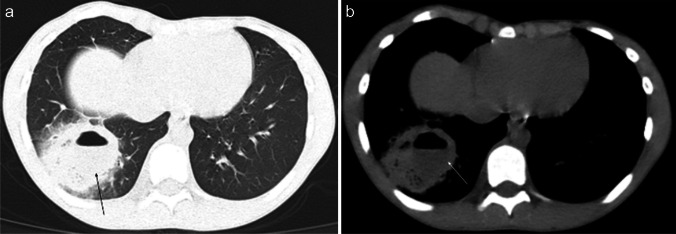

On chest radiography, an uncomplicated pulmonary hydatid cyst appears as a well-defined homogenous opacity, more commonly appearing in the lower lobes (Fig. 6). There can be multiple cysts in 30% of cases and appear bilaterally in 20% of cases. Calcification in the cyst wall makes the diagnosis almost certain; however, it is rarely seen. Complicated cysts (i.e., eroding a bronchus) can have a more heterogeneous appearance with deformed shape, air inclusions, and air-fluid levels. In such cases, CT can be especially helpful in establishing the diagnosis [57].

Fig. 6.

Contrast-enhanced computed tomography images in an 11-year-old boy with hydatid disease who presented to hospital with a 2-month history of hemoptysis, abdominal distention, and elevated inflammatory markers. The patient had a history of travel to an endemic area in the 5 months prior to presentation. Coronal lung window (a) and axial mediastinal window (b) images demonstrate a well-defined cystic mass (arrows) in the mid zone of the left lung. The cyst wall has no calcification and enhances after contrast agent injection, while the content of the cyst remains homogenously hypodense

Chest radiography is the first-line radiologic imaging that can raise suspicion of pulmonary amoebiasis when lung abscess is found. The amoebic abscess is characteristically amorphous in shape, with thick irregular walls, with or without an air-fluid level (Fig. 8). Before the formation of the amoebic abscess, consolidation within the lung and pleural effusion is seen [62]. In a country where amoeba is endemic, the differential diagnosis for thoracic abscess should include amoebic origin, especially in the presence of characteristic imaging features [66].

Fig. 8.

Posteroanterior chest radiograph in a 15-year-old boy with amoebiasis who presented to the emergency department complaining of breathlessness for the preceding 10 days shows opacity with an air-fluid level (arrow) in the right lower lobe (amoeboma) and a right-sided pleural effusion (figure from “A Rare Case of Primary Pulmonary Amoebiasis without Gastrointestinal Involvement: A Case Report” by Nugroho et al.; licensed under CC BY-SA; original cropped and annotated)